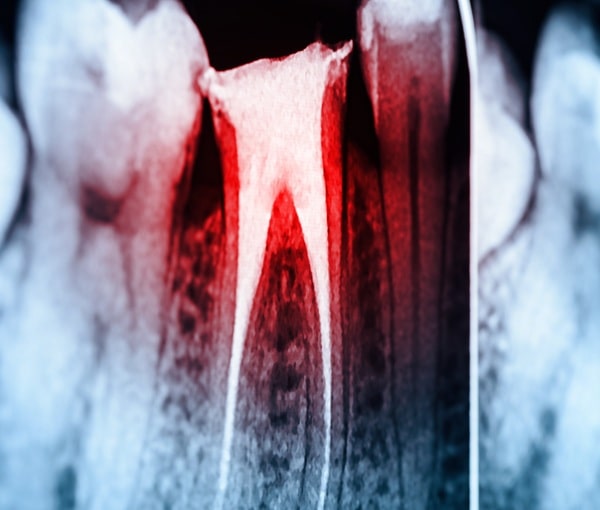

CBCT X-Ray in Regina

Treatment planning and diagnostic accuracy.

Our CBCT x-ray helps us see the structures beneath the surface, assisting us in planning complex treatments with greater confidence and accuracy.

CBCT stands for cone beam computed tomography. Unlike traditional 2D X-rays, a CBCT x-ray creates a full 3D image of your teeth, jaw, sinuses, nerves, and surrounding bone. It’s a valuable tool for diagnosis, treatment planning, and surgical preparation.

When Do We Use A CBCT X-Ray?

Planning root canal treatment

What to Expect during a CBCT X-Ray

The x-ray itself takes less than a minute. You will stand while the machine rotates around your head, capturing images from multiple angles. The result is a high-resolution 3D model that allows us to examine everything in detail — from tiny nerve and vascular pathways to bone thickness.